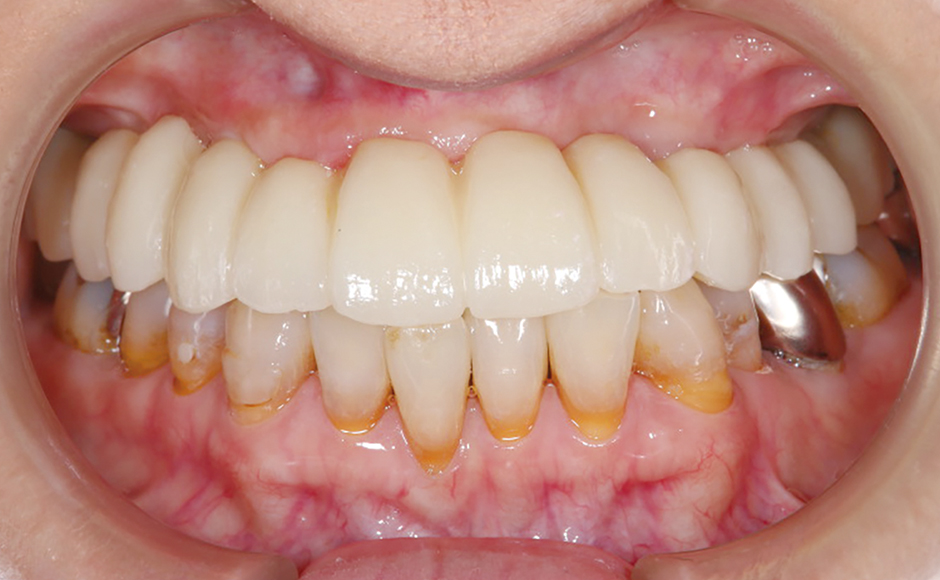

症例3:上顎残存歯を全て抜歯し、オールオン6による即時荷重